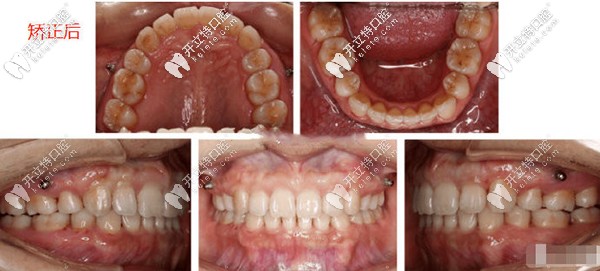

牙齒排齊

上圖就是隱適美矯正后的效果,上下頜牙齒對齊,從側(cè)面也能看得出牙齒內(nèi)收了不少,女士矯正后反饋,自己的露齦笑真的沒有了,而且五官變化還是挺大的,她覺得目前可以先不做整形啦。